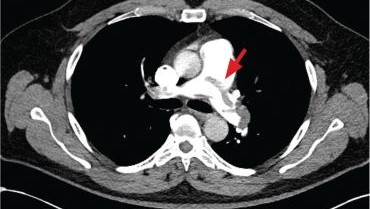

The Need for a Multidisciplinary Approach for Successful High-Risk Pulmonary Embolism TreatmentApril 8, 2025